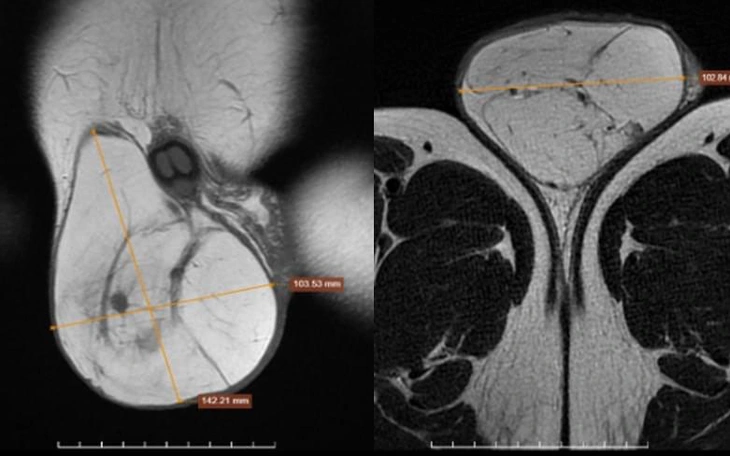

Sau khi được khám lâm sàng, chụp cộng hưởng từ (MRI), các bác sĩ chẩn đoán bệnh nhân mắc u phần mềm khổng lồ vùng vai phải, cần phẫu thuật để tránh biến chứng chèn ép cơ, mạch máu và thần kinh.

Trực tiếp thực hiện ca mổ, TS Bùi Sỹ Tuấn Anh, Giám đốc Bệnh viện Giao thông vận tải, cùng các bác sĩ đã cẩn trọng bóc tách, cắt trọn khối u nặng khoảng 1,5kg. Đồng thời bảo tồn tối đa các cấu trúc cơ, mạch máu và thần kinh vùng vai để đảm bảo chức năng vận động cho người bệnh.